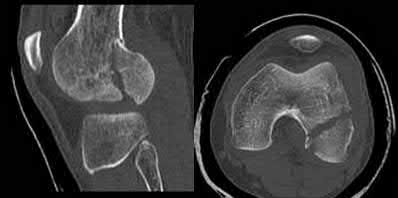

A 25-yo man sustains the injury shown in Figures 29a and 29b as a result of high-speed trauma. Examination reveals diffuse weakness in the lower extremities that is slightly worse on the right side, and decreased rectal tone and sensation. A CT scan is shown in figures 29c and 29d. Definitive treatment of the injury to the spine is delayed because of a severe pulmonary contusion. At 15 days after the injury, the patient’s neurological status remains unchanged. Management should now consist of